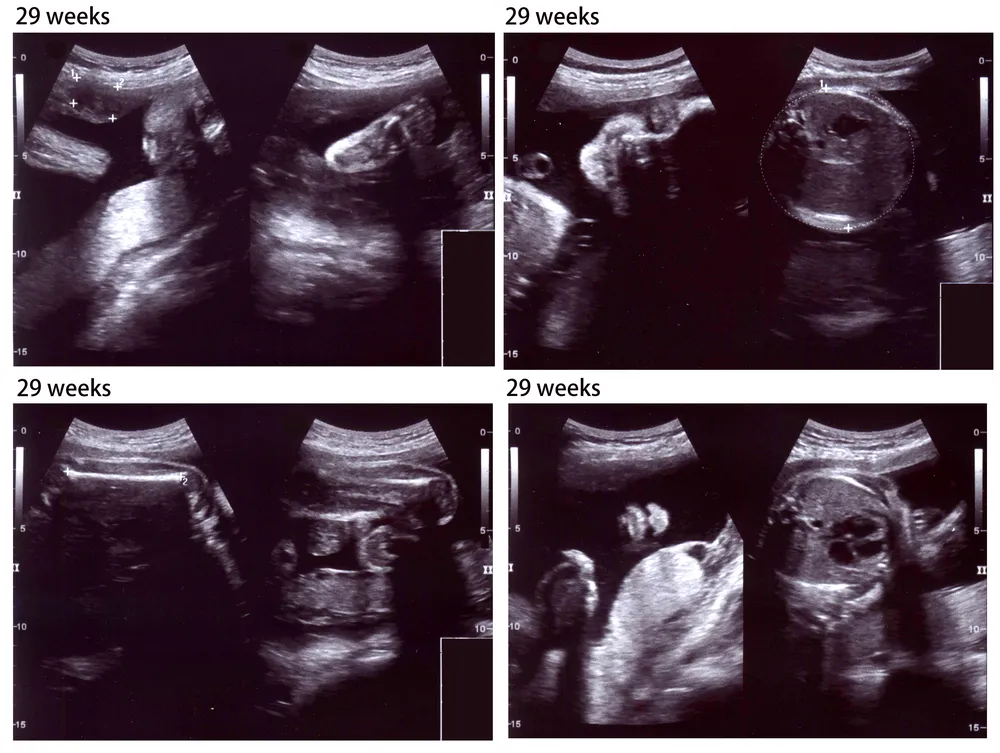

Tuần này, hình thức siêu âm thai sẽ cho thấy em bé phát triển nhanh như thế nào. Vậy, thai nhi 29 tuần tuổi phát triển như thế nào? Hiện tại, em bé đang trong giai đoạn phát triển và có những thay đổi đáng kể trong quá trình tăng trưởng nói chung.

- Trên hình ảnh siêu âm, thai nhi có thể trông hơi mũm mĩm hơn trước. Con đang có một chút mỡ trắng dưới da, bên cạnh lớp mỡ nâu trước đó. Làn da của bé cũng trở nên mịn màng hơn.